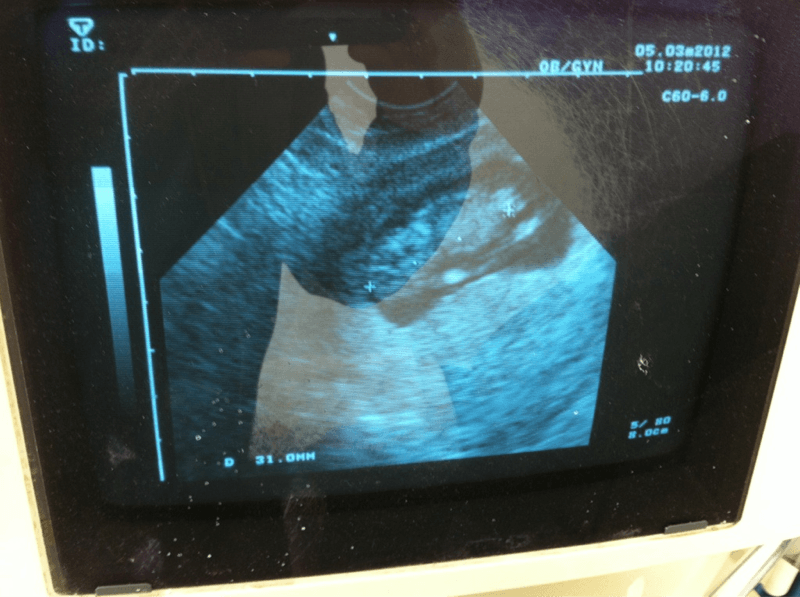

perri-ne voila ma fille a 9sa

Pièces jointes

• S6003882.JPG

S6003882.JPG

34.2 KB · Affichages: 153